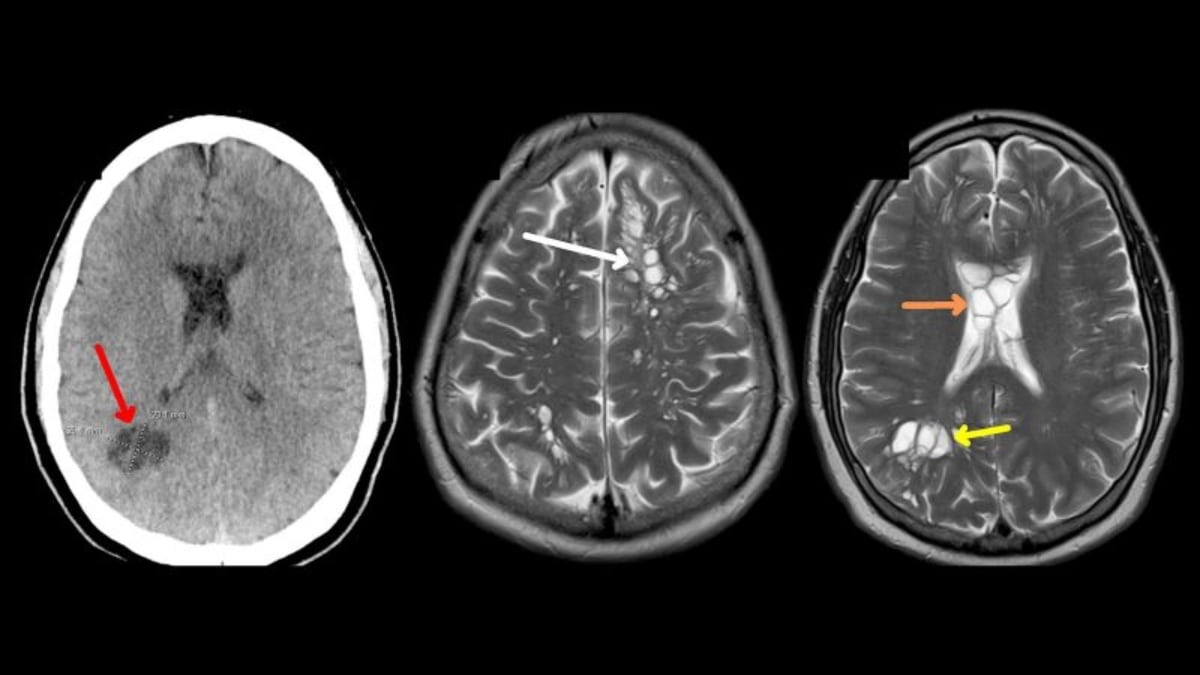

Así pues, tras efectuar una evaluación con estudios más detallados, lograron descubrir que en su cerebro se alojaban decenas de larvas ocasionando los dolores de cabeza.

Esto porque luego de asistir a numerosas consultas al hospital, los médicos encontraron que la razón de las molestias era que en su cerebro vivían decenas de larvas.

El diagnóstico dado fue “cisticercosis”, una infección causada por larvas como las que se alojaban en su cuerpo.

Y se logró definirlo luego de que los especialistas estudiaran la alternativa de que extrañas masas en su cerebro eran consecuencia de un padecimiento neurológico.